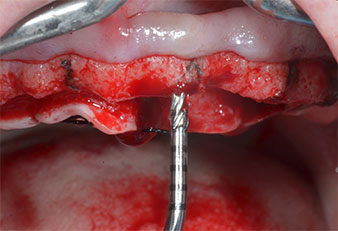

A flame-shaped, diamond-coated piezoelectric instrument (Piezomed I1) was used to mark the implant positions and to perform pilot preparation (Fig. 3). Care was taken to use an up and down movement, with reduced power, full irrigation and low pressure (below 300 g). Next a pilot instrument (Piezomed I2A/I2P) was applied for the initial 2 mm diameter enlargement of the implant sites (Fig. 4), followed by a 3 mm insert (Fig. 5).

Ultrasonic marker instrument Piezomed

Fig. 3: Preparation with the ultrasonic marker instrument Piezomed I1 is performed in an up and down movement, parallel to the long axis of the working part.

Piezomed I2A/I2P instruments

Fig. 4: The next step is pilot enlargement with the Piezomed I2A/I2P instruments, which are applied in a rotary horizontal movement.